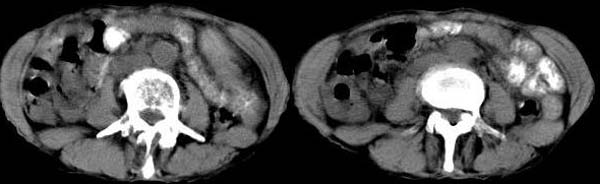

男 74岁,聋哑人,病史不详。

升结肠壁不均匀增厚,周围境界尚清,腹主动脉旁、盆腔内未见肿大淋巴结,考虑:升结肠癌可能性大.

升结肠壁明显不规则增厚,呈偏心性,考虑结肠癌。

右半结肠不规则 弥漫性增厚,与周边胀器分界清楚,建议行钡剂灌肠.单纯本片还是考虑:升结肠癌.

升结肠壁不均匀增厚,肠腔偏心性狭窄,周围境界尚清,腹主动脉旁、盆腔内未见肿大淋巴结,考虑:升结肠癌可能性大.建议:纤维结肠镜检查.